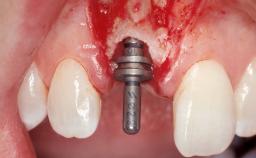

A 33-year-old female patient presented with an upper left central incisor that required extraction after a failed endodontic therapy. The tooth had been traumatized when the patient was a teenager and had undergone several endodontic treatments, including two apicectomy procedures. The patient was in good health and did not smoke. Clinical examination showed that the patient had a high lip line. In full smile, the gingival margins of the upper teeth were visible to the first molars. The gingival margins of central incisors 11 and 21 were only just showing. Examination of tooth 21 confirmed that the tooth was mobile and had hypererupted by 1 mm.

Placement Protocol | Immediate implant placement |

Tooth Site | Maxillary incisor or canine |

Socket Morphology | Single-root socket |

Socket Integrity | Damage to one or more bone walls |